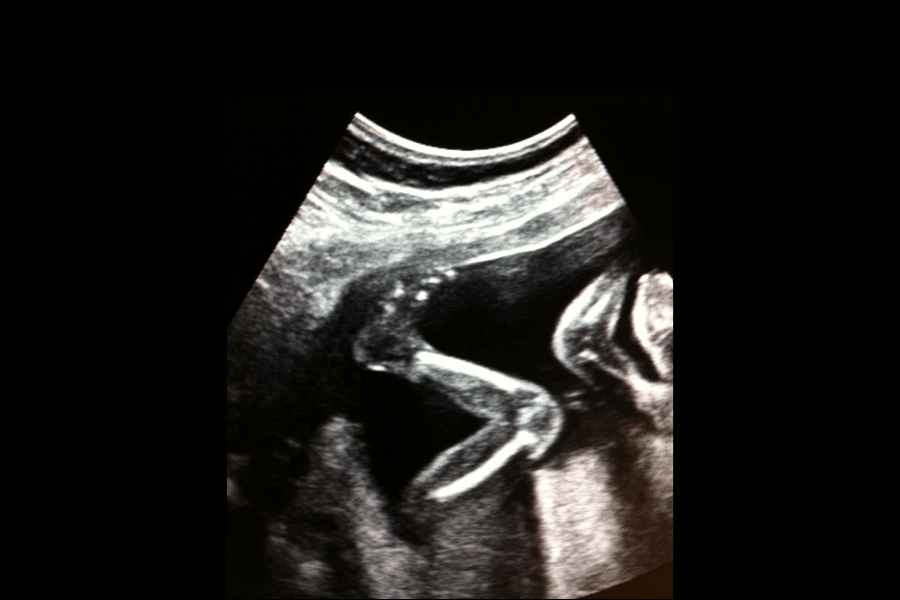

La façon dont l’enfant bouge dans le ventre de sa mère varie d’un individu à l’autre. Les moments où il s’agite et l’intensité de ses mouvements sont propres à chaque enfant. L’enfant effectue aussi de petits mouvements qui sont difficiles voire impossibles à percevoir. L’enfant donne des coups, s’exerce à respirer et à avaler, développe ses réflexes préhenseurs et sa capacité de succion. Il n’y a pas que le fameux coup de pied.

Votre perception des mouvements fœtaux est étroitement liée à la personnalité de l’enfant, à sa marge de manœuvre, à son orientation dans l’utérus et à la position du placenta.